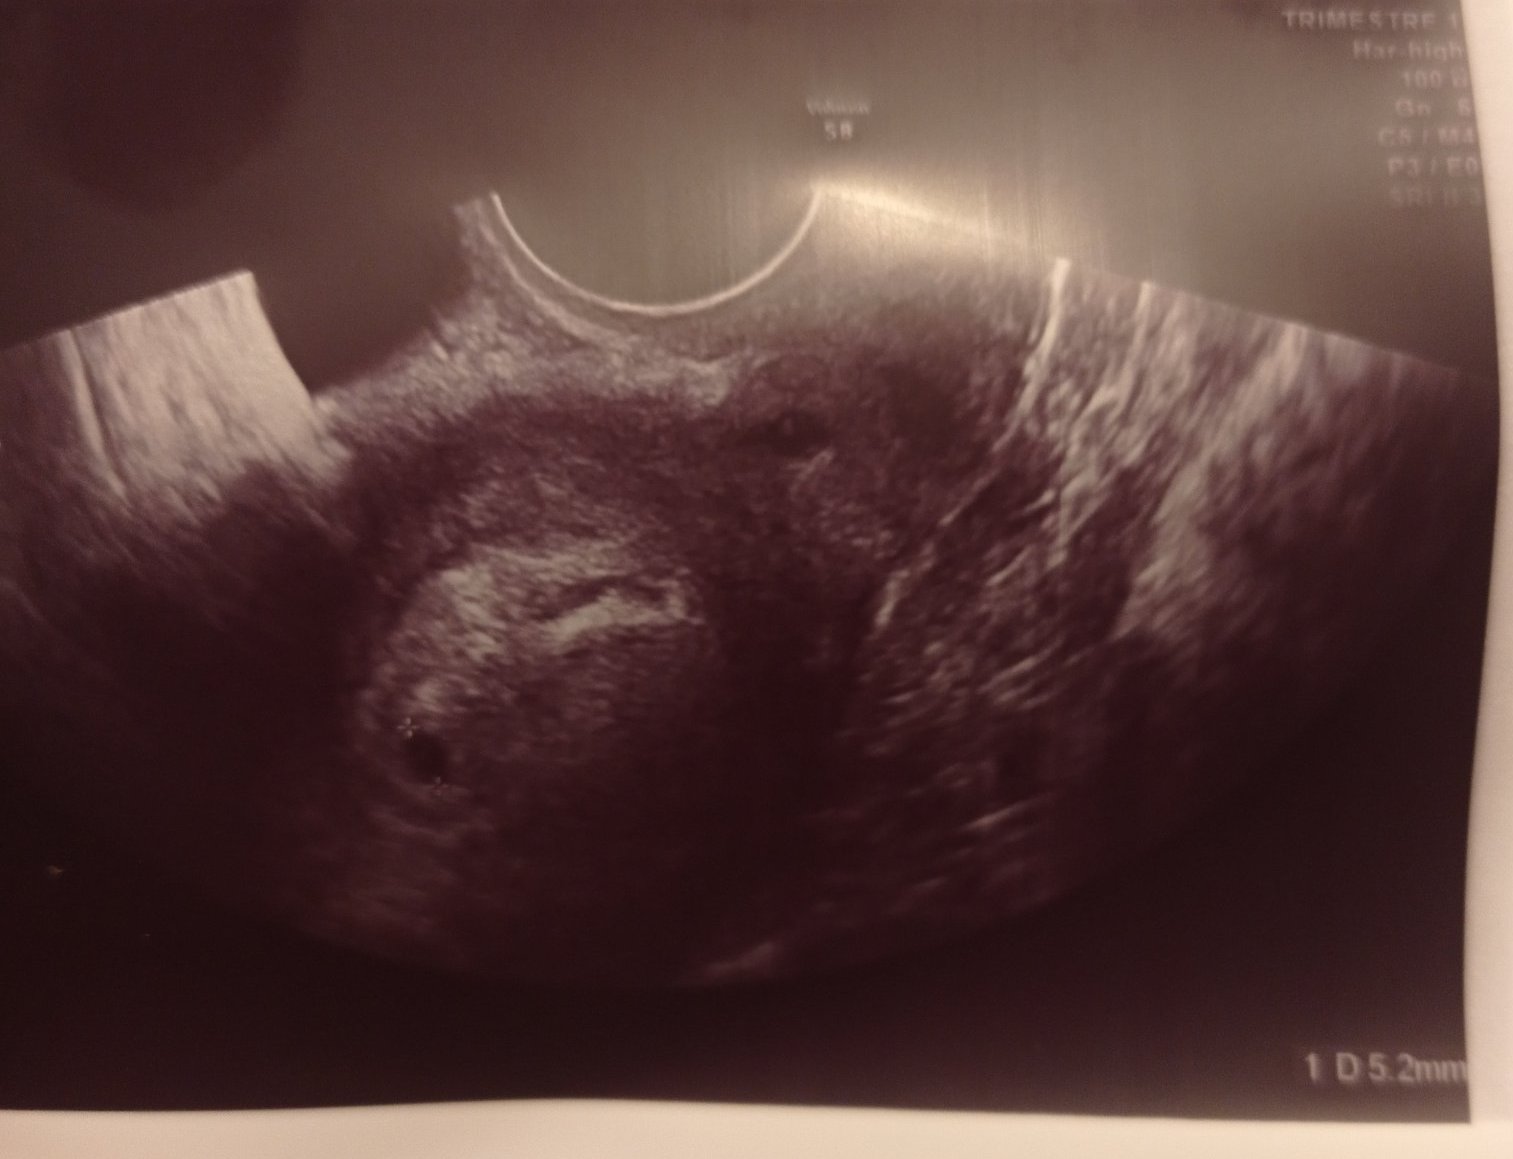

И при мен е подобно положението ,доколкото разчитам сакчето е било 5.2 см при 10 дни закъснение на цикъла (5+3)

Не се видя ембрионче,нито жълтъчно мехурче.Чакаме 🙂

Ето снимка